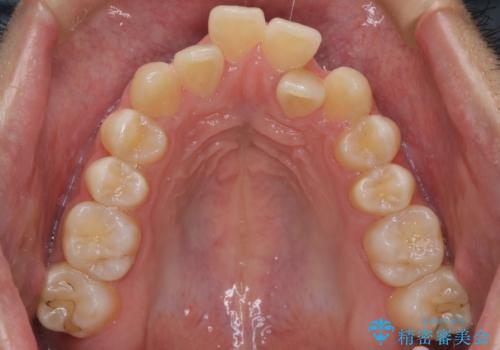

- 前歯の凸凹を主訴に来院されました。

上の歯のアーチが狭窄していたため、骨の幅を広くするためにMSE(急速拡大装置)を使用してからインビザライン にて治療を行いました。